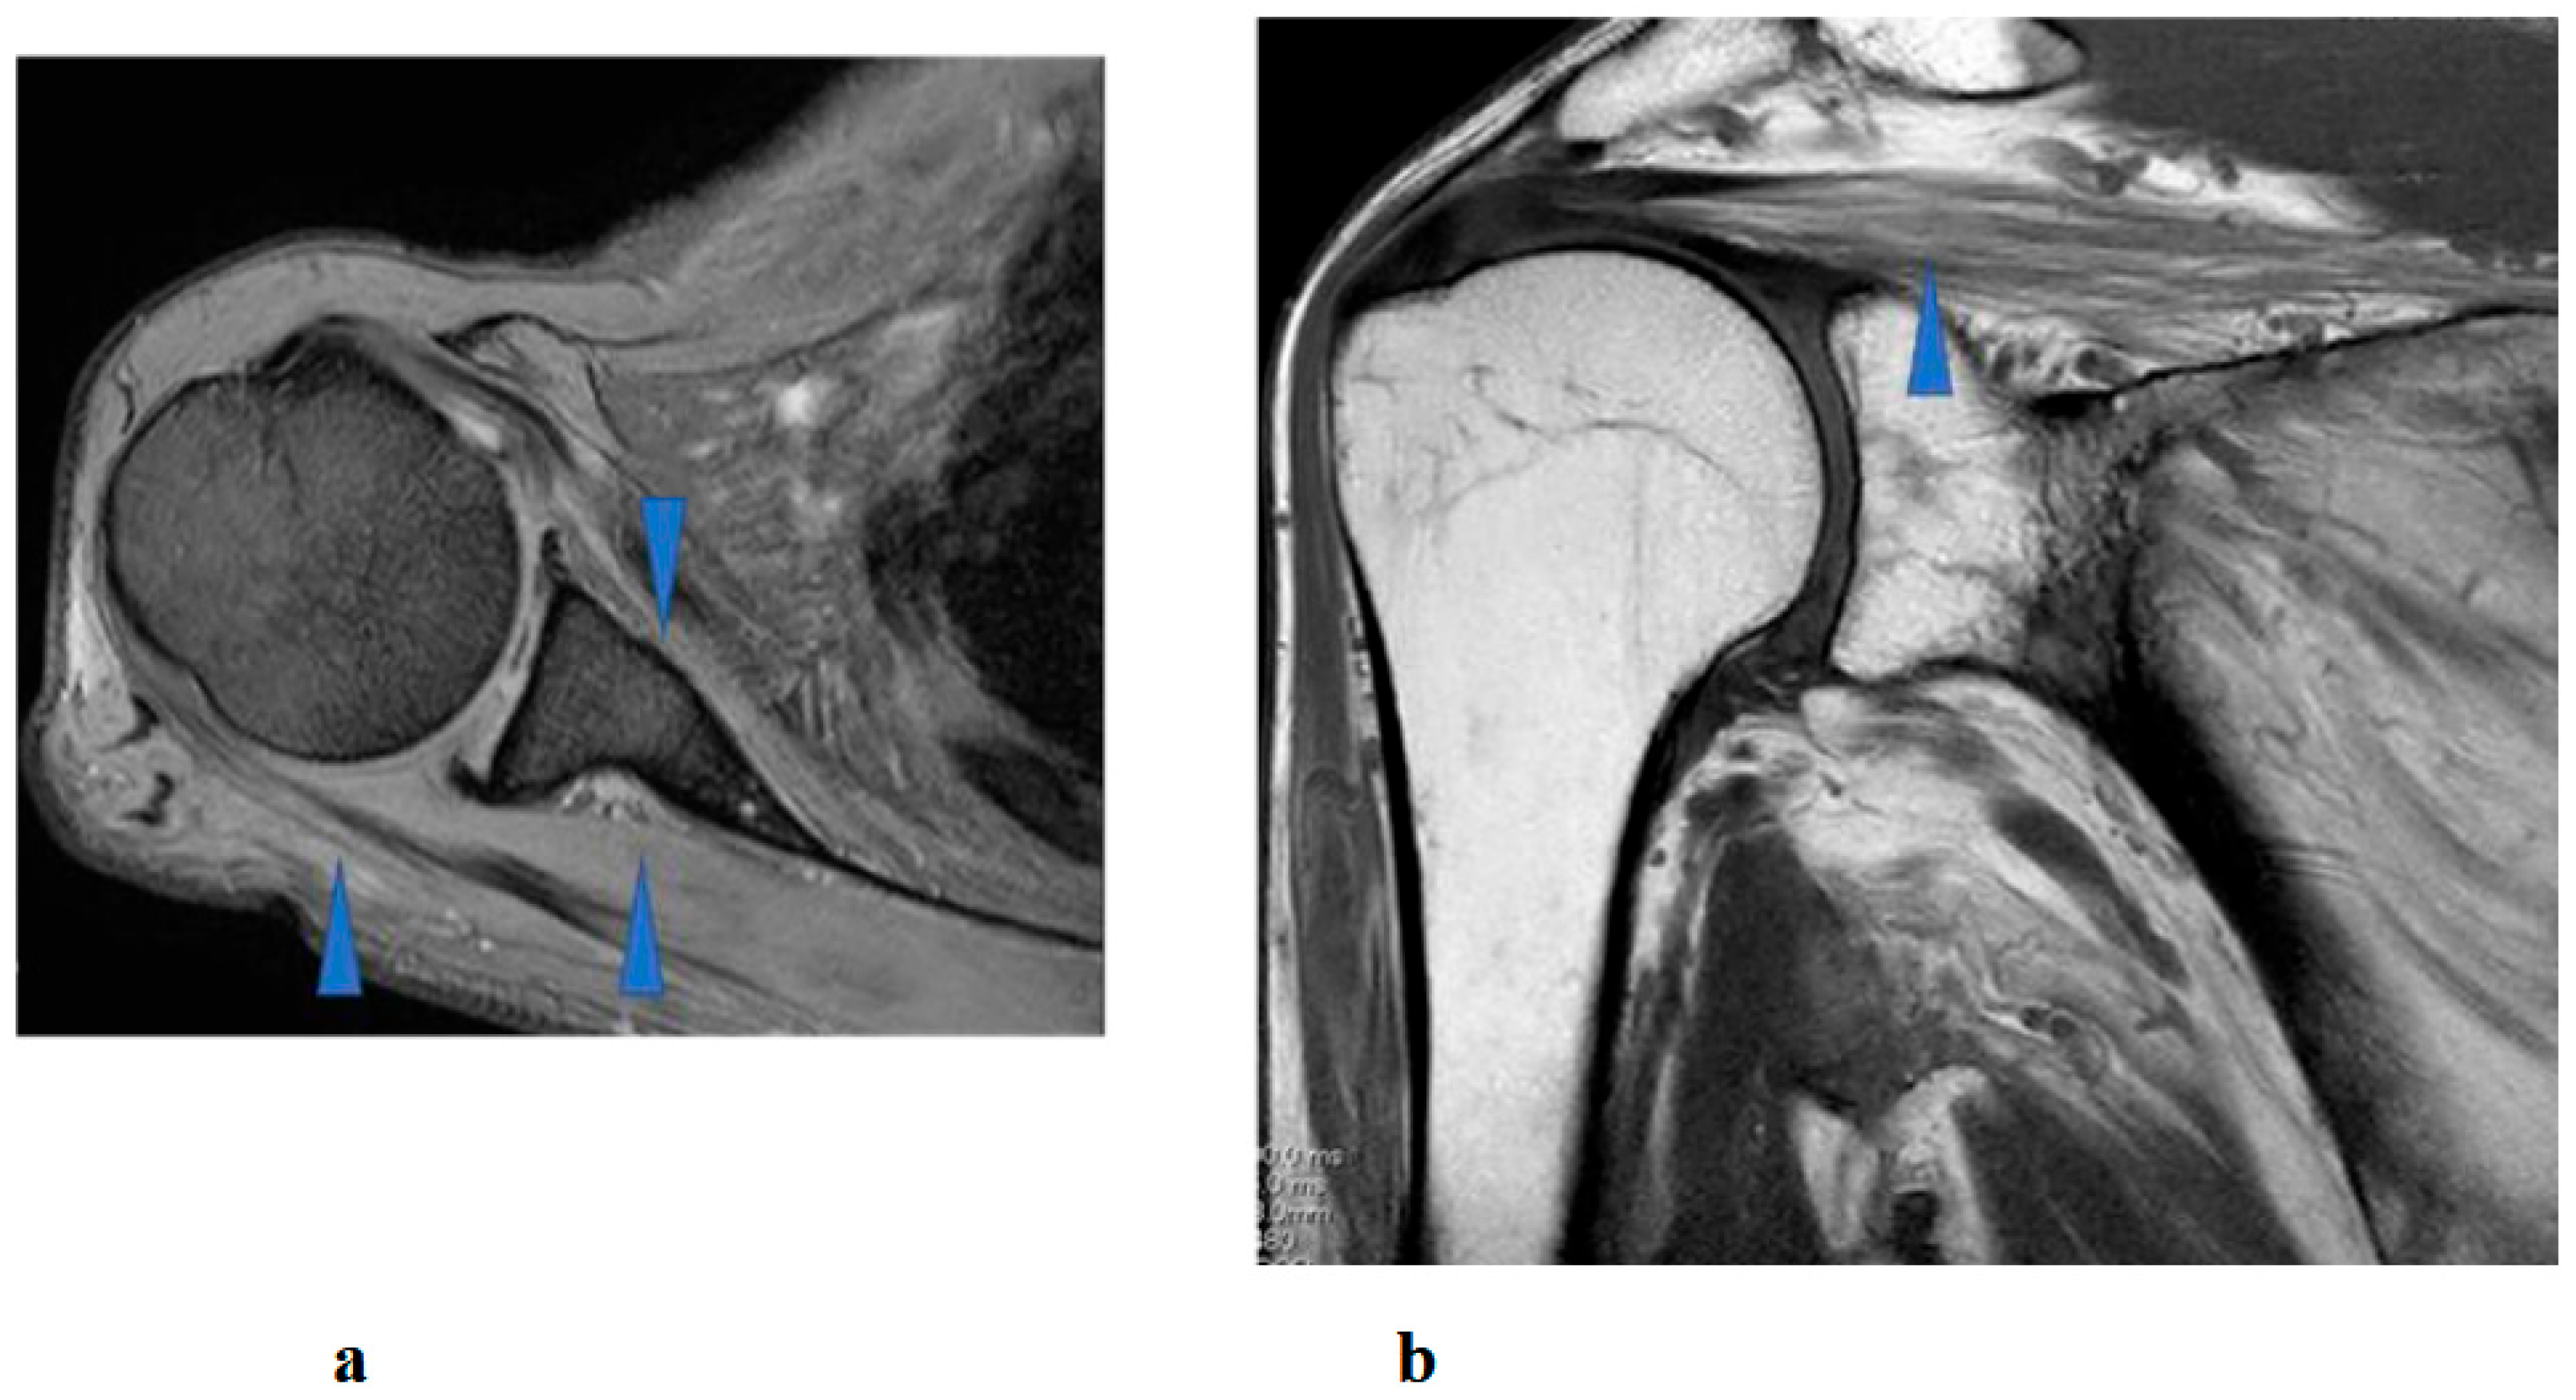

Figure 2.

Preoperative (a,b) and postoperative (c,d) images following the first surgery, as well as postoperative images from the second surgery (e–g). (a) Lateral cervical spine X-ray showing narrowing of the intervertebral disc space and osteophyte formation at C5–C6 and C6–C7. (b) Reconstructed mid-sagittal CT image after myelography revealing spinal cord compression at C5–C6 and C6–C7, and posterior displacement of the C5 vertebral body. (c) Postoperative lateral cervical spine X-ray after anterior decompression and fusion at C5–C6. (d) Mid-sagittal cervical MRI demonstrating persistent spinal cord compression from C3–C4 to C6–C7. (e) Postoperative lateral cervical spine X-ray after C4–C6 laminoplasty and partial laminectomy at the caudal aspect of C3 and the cranial aspect of C7. (f) Mid-sagittal cervical MRI showing adequate spinal cord decompression from C3–C4 to C6–C7. (g) Axial CT image at the C5–C6 level showing adequate right C5–C6 foraminotomy (arrow).

A 46-year-old man presented to the outpatient clinic of our hospital with a chief complaint of right-sided C5 palsy that had persisted for 41 months following cervical spine surgery (Figure 1). At the age of 43, he noticed a decrease in grip strength in his right hand and numbness in his right upper limb, and visited another hospital. Examinations at that hospital revealed that his initial symptoms were caused by cervical spondylotic myelopathy due to spinal cord compression from degenerative cervical vertebrae (Figure 2a,b). Based on the diagnosis, at that hospital, he underwent anterior decompression and fusion surgery at the C5–C6 level (Figure 2c). Prior to initiation of HAL therapy at our hospital, his neurological assessment was as follows: Numerical Rating Scale for pain = 4, American Spinal Injury Association (ASIA) motor score = 97, and ASIA sensory score = 108.

Postoperative imaging revealed spinal cord compression extending from C3–C4 to C6–C7 (Figure 2d). Based on the imaging findings, inadequate spinal cord decompression from the initial surgery was diagnosed, and he underwent an additional cervical spine surgery at the same hospital 20 months later. The second surgery consisted of C4–C6 laminoplasty and partial laminectomy at the caudal aspect of C3 and the cranial aspect of C7 (Figure 2e). During the procedure, surgical intervention for post-operative C5 palsy was concurrently undertaken, specifically a right C5–C6 foraminotomy.

Two days after the second surgery, he experienced pain extending from his neck to his right shoulder, followed by difficulty in elevating his right upper limb. Postoperative MRI demonstrated adequate spinal cord decompression with no obvious abnormal findings (Figure 2f). Post-operative CT confirmed the right C5–C6 foraminotomy was appropriately performed (Figure 2g, arrow).